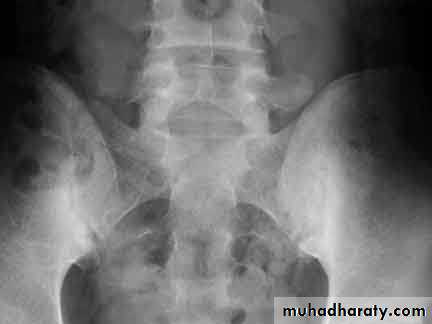

DEVELOPMENTAL DYSFLASIA OF HIP (CONGENITAL DISLOCATION OF THE HIP)

• An abnormally lax joint capsule allows the femoral head to fall out of the acetabulum, leading to deformation.• Predisposing factors for the development of CDH are:

• * Abnormal ligamentous laxity (effect of estrogen; fema1e:male = 6:l)

• * Acetabular dysplasia .

• CDH occurs most commonly (70%) in the left hip. Bilateral involvement is seen in 5%.

• Radiographic features

• US (commonly used today) at 1-3 months

• * Normal femoral head is covered at least 50% by acetabulum , In CDH < 50% of femoral head is covered by acetabulum .

Plain film

At 3-6 months :By doing special veiw (Von Rosen veiw )by abduction of the thigh 45 degree and internal rotation .

In DDH the lines that drown through the femura will meet in higher level than the normally should at lumbosacral joint .

6 months and later

* AP veiw ( femural epiphysis are visualized ):* Superolateral displacement of proximal femur (disturbed shenton’s line )

* Increase in acetabular angle

* Small capital femoral epiphysis

Femoral head is located lateral to Perkin's line

* Other features that are sometimes present

Abnormal sclerosis of the acetabulum

Shallow acetabulum

Formation of a false acetabulurn

Delayed ossification of femoral head